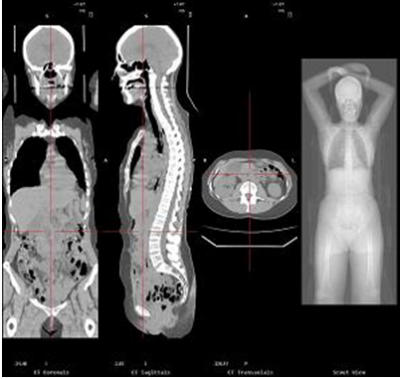

Figure 5 : Image scanner offrant une étude anatomique précise.

Ainsi, la TEP repère les cellules ayant un métabolisme anormal, particulièrement les cellules cancéreuses et le scanner permet de situer les images obtenues à la TEP dans leur environnement anatomique. Il profite donc des fonctions de ces deux formes d'imagerie et les assemble.